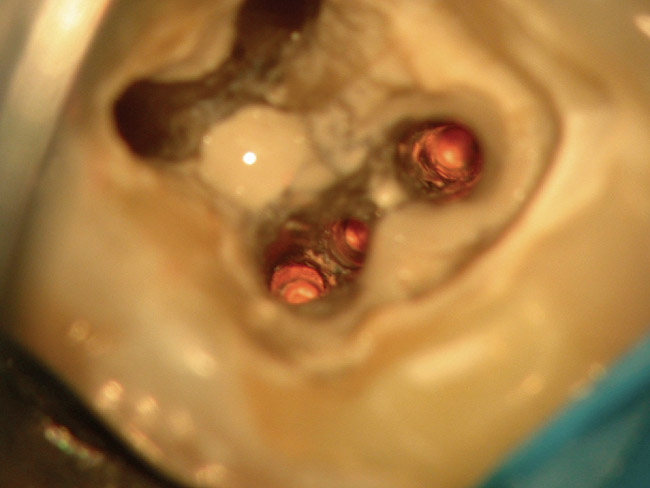

Figure 4b  The patient was asymptomatic, and periodontal probing depths were within normal limits; however, a new crown restoration was planned. Nonsurgical endodontic re-treatment was initiated. The intracoronal picture shows the previously treated 4 canals with infected gutta-percha filling.

Figure 4b

Figure 4c  Under high magnification, a furcation canal (Figure 4C) and a third distal canal (Figure 4D) were located.

Figure 4c

Figure 4d  Under high magnification, a furcation canal (Figure 4C) and a third distal canal (Figure 4D) were located.

Figure 4d